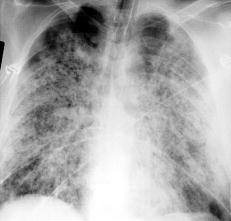

一般肺部症狀可先於腎臟表現數天數周、或數年出現肺部出血可輕可重,也可嚴重至危及生命。大量或持續出血可發生缺鐵性貧血。一旦出現胸痛應注意排除系統性紅斑狼瘡血管炎或肺栓塞等病變肺部X線顯示彌散性點狀浸潤陰影從肺門向外周散射,肺尖常清晰。咯血和肺部浸潤是肺部病變的特徵。